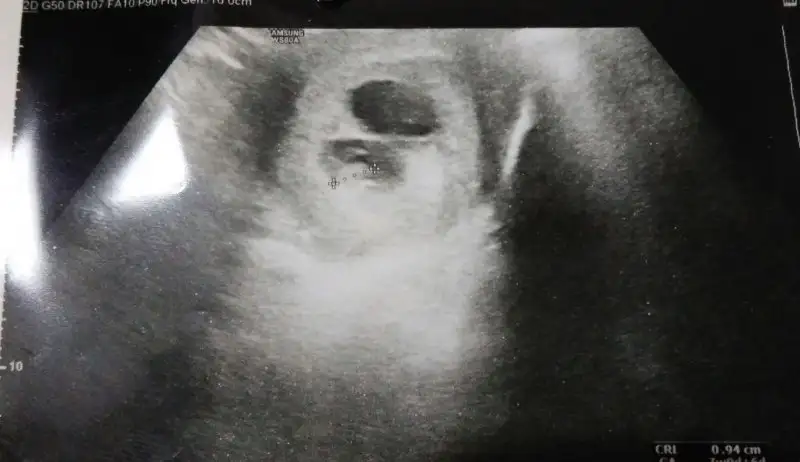

7.hafta usg bakabilirmisiniz?

• IMG-20180409-WA0001.webp

14 KB · Görüntüleme: 238

• IMG-20180409-WA0002.webp

16 KB · Görüntüleme: 189